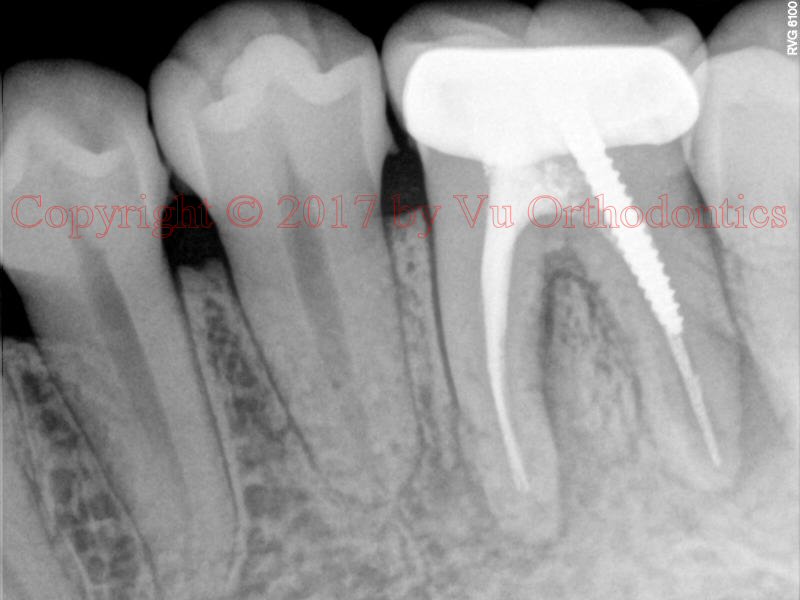

Example 2: RCT (root canal therapy)

Fig. 5 Periapical radiograph, showing a limited view of the bone damage